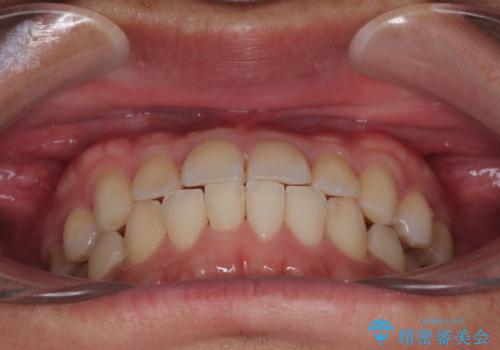

今回ご紹介するのは、「前歯のガタガタ(叢生)」と「奥歯のかみ合わせ(シザーズバイト)」にお悩みでご来院された患者様の症例です。

▼ 診断

・上顎左右の第二大臼歯が頬側へ転移し、シザーズバイト(scissors bite)の状態

・上顎左側第二小臼歯が90度捻転しており、噛み合わせに影響

**前歯のデコボコ(叢生)**が整い、歯列全体が美しく改善

シザーズバイトの奥歯も正常なかみ合わせに改善

捻転歯も回転が修正され、全体的に清掃性・咀嚼効率が向上